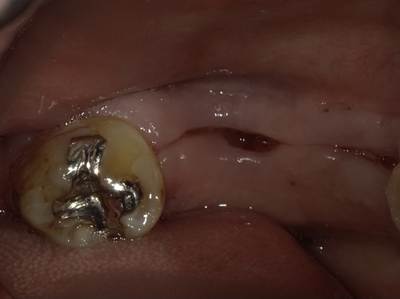

移植歯の固定と咬合調整:症例1-6

右下8番を左下6番部に植立